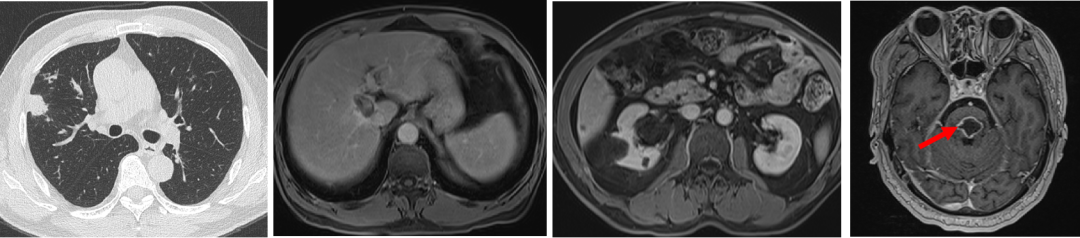

2020.5.28 复查示肝脏及脑干病灶稳定,肺部结节略增大。

2020.5.30至2021.5.25 行卡培他滨+贝伐珠单抗治疗,期间疗效评价SD。

2021.11.25 复查疗效评价为SD。

患者症状明显改善:右侧肌力IV级。